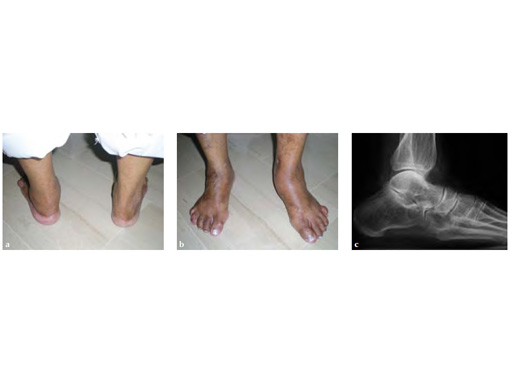

Progressive weight bearing was permitted at 8 weeks and UCBL was advised until the fourth postoperative month (see Fig 3a-b).